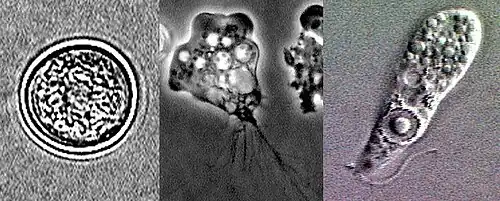

Différents stades d'E. histolytica.

Trophozoïte d'Entamoeba histolytica.

Kyste d'Entamoeba histolytica.

Morphologie

Le genre Entamoeba se caractérise par un noyau ayant l'aspect d'un anneau après coloration, avec une chromatine disposée en petit amas central (dit caryosome) et en couche périphérique.

Entamoeba histolytica peut se présenter sous deux aspects différents : le trophozoïte, forme cellulaire végétative mobile et de multiplication, et le kyste, forme immobile, de résistance et de contamination[11].

Le trophozoïte présente à son tour deux formes :

• Entamoeba histolytica minuta, de petite taille (en latin : minuta signifie « petit »), soit 10 à 15 µm. C'est une forme infestante qui se comporte en saprophyte restant à l'intérieur du colon, et qui ne donne aucun symptôme (sujet «porteur sain»).

• Entamoeba histolytica histolytica, plus volumineuse, de 20 à 30 ou jusqu'à 40 µm. C'est une forme invasive, véritablement parasitaire, hématophage, qui envahit la muqueuse colique et peut migrer vers d'autres organes, en étant responsable de l'amœbose maladie.

Entamoeba histolytica histolytica présente le même aspect général que minuta, avec des caractères supplémentaires, comme la présence d'hématies en voie de digestion dans des vacuoles cytoplasmiques (d’où le nom d’histolytica)[11].

Le kyste (10 à 16 μm) est sphérique, entouré d'une enveloppe résistante. Initialement, un kyste immature contient une vacuole stockant du glycogène, des agrégats de ribosomes, et un noyau. Par division du noyau, le kyste mûrit en deux puis quatre noyaux pour devenir un kyste à pouvoir infectieux[17]. Il survit au minimum 10 jours à 18 °C, ou 3 mois à 4 °C, dans le milieu extérieur[18]. C'est la forme de dissémination, qui résiste bien aux agents chimiques.